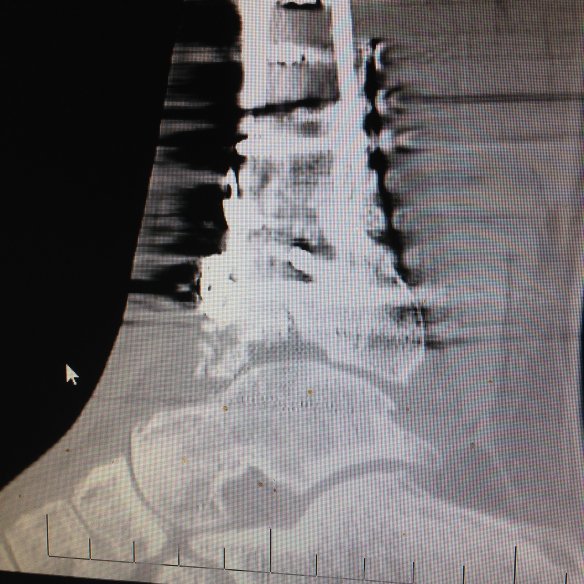

Currently I have no joint space (its bone on bone) throughout 85% of the tibiotalar joint. The joint collapsed at about 1 year post surgery. My surgeon said that is typical. The time it takes for the damaged “chondrocytes” to die takes about a year. About 15%of my chondrocyres survived the accident. And somehow miraculously that little bit of cartilage gives me the ability to walk around. (if I limit my range of motion to just that area).

Here is my recent CT side view. https://goo.gl/photos/jb7izRNTi5tkskro9